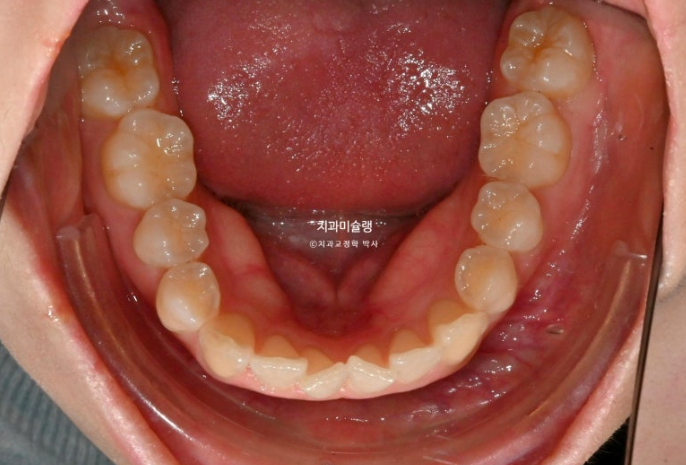

14개 장치를 2월부터 6월까지 모두 낀 후 모습입니다.

중심선은 상당히 개선되었으며 덧니는 잘 배열 되었습니다.

송곳니 주변에 공간이 남아있으며

덧니 배열이 완벽하진 않습니다.